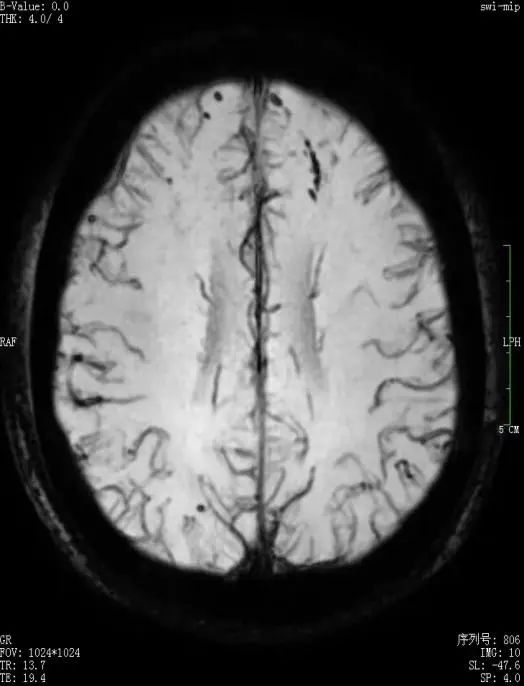

1.5T(左)3.0T(右)头颅磁敏感对比